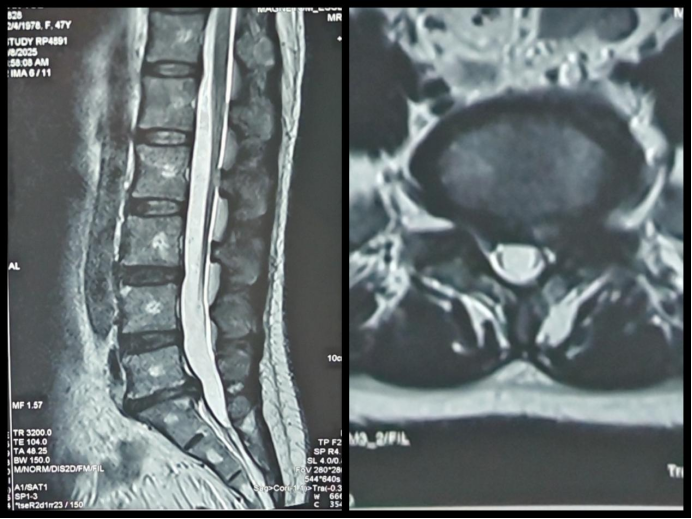

术前腰椎核磁图像